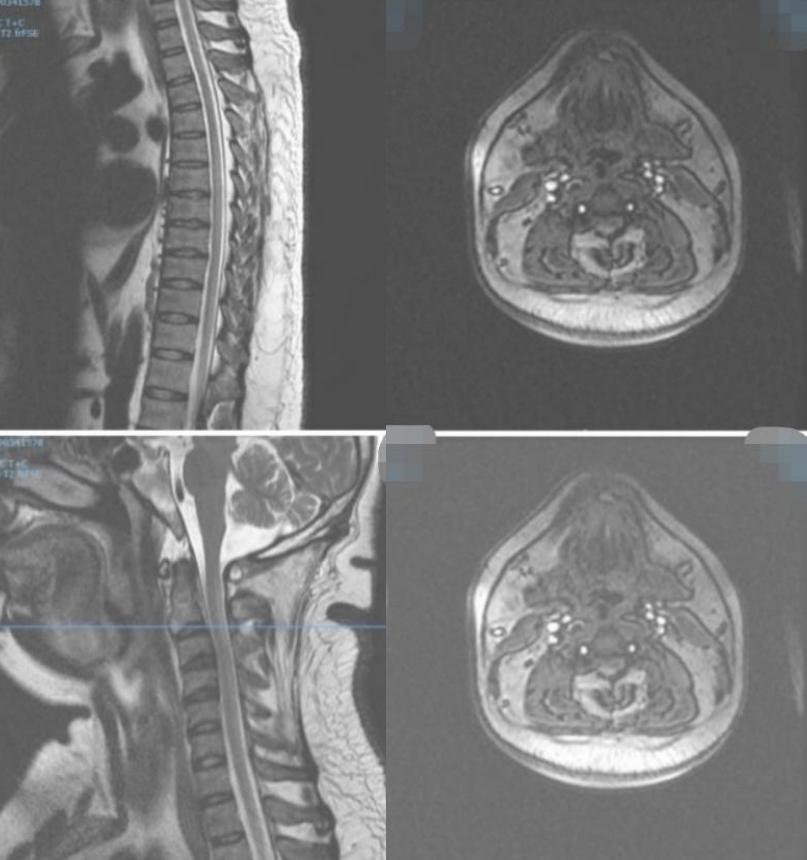

男性34岁,肢体麻木无力1月余入院。查体:神志清,双上肢肌力5级,双下肢4+级,远端4级,左上肢触觉轻度减退,双下肢触痛觉,振动觉明显减退,外院激素冲击治疗5天症状无改善。

答案:脊髓亚急性联合变性。维生素B12摄取、吸收、结合与转运的任何一个环节出现障碍均可引起维生素B12缺乏。内因子抗体和(或)抗胃壁细胞抗体阳性的SCD患者需要长期肌肉注射维生素B12。笑气中毒也是脊髓亚急性联合变性的重要原因,需要注意个人生活接触史。除了经典的反兔耳征/八字征/倒Ⅴ字征,脊髓亚急性联合变性还可以表现为圆点征、小字征、三角征。脊髓亚急性联合变性还需要与铜缺乏性脊髓病、维生素E缺乏性脊髓病、艾滋病相关性脊髓病鉴别。

答案:脊髓硬膜外血肿。补充病史既往长期服用华法林。患者临床以麻木,肢体无力卒中样起病。但是有颈部疼痛病史,病史跟影像提示脊髓硬膜外血肿。脊髓硬膜外血肿可能是自发的,也可能是继发于创伤、凝血功能障碍或麻醉操作。危险因素包括高龄、女性、创伤、血管畸形、抗凝治疗和高血压。提醒注意的是这样的患者有可能在绿色通道中被当做急性卒中患者被溶栓。

病例10

男性68岁,四肢末梢麻木2月余,伴有站立不稳,加重1周,不能独立行走。查体双侧跟膝胫试验欠稳准,双侧位置觉、震动觉减退。

答案:脊髓亚急性联合变性。患者老年男性,亚急性病程,以深感觉受累为主要表现,脊髓影像长节段病灶,轴位显示后索病灶“圆点征”,颅内影像改变无特异性,NMOSD相关抗体检测以及OB均阴性。其特征性影像有“圆点征”、“小字征”、“三角征”、“八字征”等。